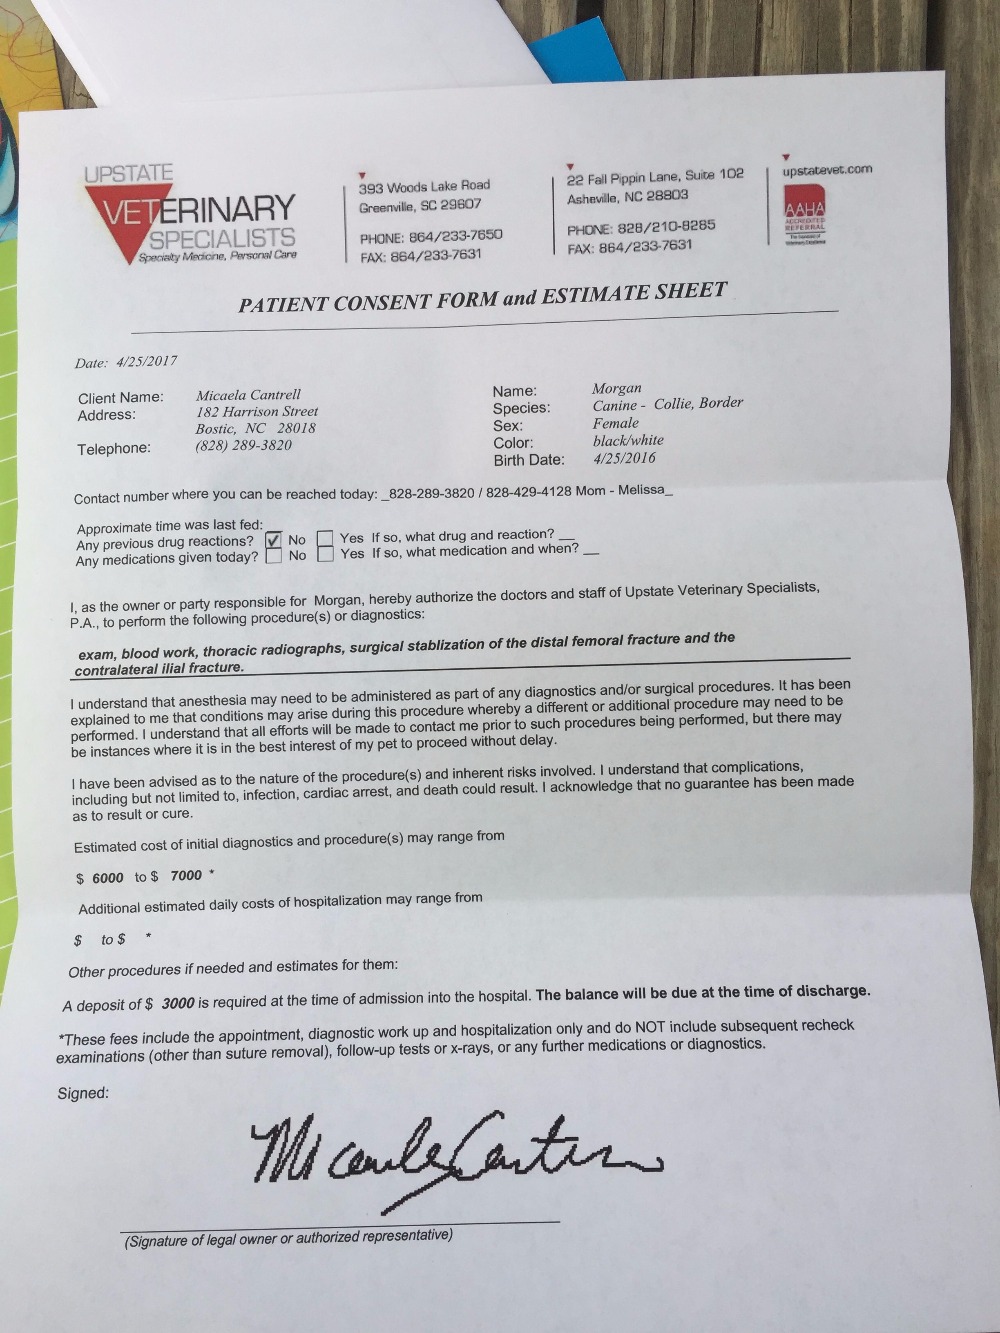

So the latest update (4/25 at approx 6:30 pm) is that i went ahead and took the leap and drove Morgan up to Upstate Veterinary Specialists in Greenville SC, to see if they would accept us, since we couldn't get an appt. until tomorrow, which I feel like would be pushing it (plus I have to go back to work!) The good news is, they agreed to see her and accept her, and her surgery will happen tomorrow. They did additional scans and bloodwork to make sure all organs looked good, and she tested HW negative with noraml bloodwork results! The bad news is the price has (once again) gone up, and this is betting on everything goes as planned. I paid the $3000 today out of pocket, so that plus my lovely crown I had to have this morning (also out of pocket) put me at pretty much the most money I've ever spent in one day in my life! Below are pics of her care team as well as the surgery estimates and reciept. Everyone at the clinic was amazed that I was willing to spend this money on a dog I only just met a few days ago, but I had to tell them we had a whole team behind us, and it is all of us together that are helping. I am merely the vessel upon which she was delivered, the rest of the animal warriors are right behind us. THANK YOU again to everyone. I will continue to keep you updated (and try not to annoy you). Surgery is set for tomorrow, and I will get a call in the morning giving me a timeline for time of surgery, recovery, and when she gets to come back home! It will be a little harder for me to keep everyone updated while I'm at work tomorrow, but I will do my best!

Met with the surgeon that was to repair the broken femur this afternoon, and it is concluded that she will need a plate in her pelvic bone and her femur. He will not be able to perform the pelvic surgery and therefore she will have to go a Orthopedic Specialist. Cost has escalated from $1,200-$1,500 to now $2,000-$5,000 (not including aftercare). I will not be able to pay for this surgery in full, but I'm telling you this dog deserves it. At least half of the $5,000 needs to be raised in order to proceed, and we have very little time. If the money is not raised in time (by the end of 4/25/17) I will refund in full the money to all that have donated. Please, Please I beg of you to help me save her life.